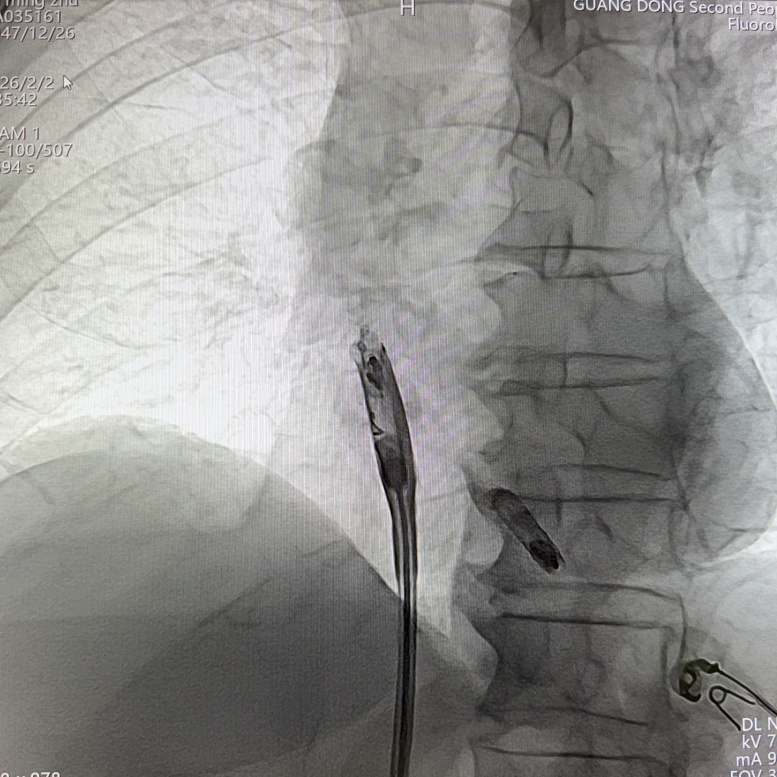

体外对接心室无导线心脏起搏器,先将心室AVEIR™ VR推送至下腔静脉与右心房交界处,在血液中激活器械,体外搜索器械信号形成连接。在保护套筒覆盖下,操纵输送导管让AVEIR™ VR跨过三尖瓣,送入右心室,定位测试参数优秀, 术中可见损伤电流明显上升,提示起搏器与心肌接触良好。接着顺时针旋转控制旋钮,将起搏器旋入1.5圈后,进入对接栓模式,摇摆测试,见起搏器头端稳定,V型标志未转动,提示固定良好,完成心室无导线心脏起搏器植入。

RAO 30°体位下,缓慢推送导管,直至保护套筒位于右心耳底部,使用解剖标记/猪尾导管造影确定右心耳的部位和右心耳的深度,当观察到“雨刷”摆动后停止推进;在透视下解锁保护套筒,保持起搏器不动,完全回撤保护套筒,观察到头端螺旋没有位移,且导管形态张力合适。